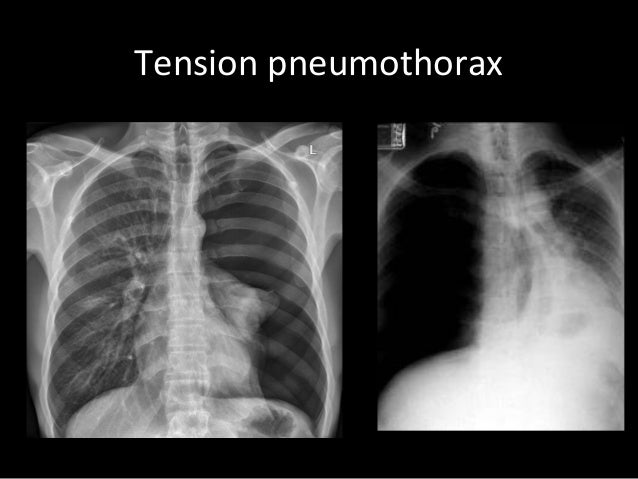

A structured approach to interpretation of the chest x ray. Chest x ray is probably the most common imaging test. The patient should be sat up in the film. Chest x ray basic interpretation by vikram patil 37831 views. Look for lung and pleural pathology. L these two lobes are separated by a major fissure, identical to that seen on the right side, although often slightly more. These images were saved with anonymous biodata for iom radiology collection and teaching purposes. Both lungs should be well expanded and similar in volume.

Learn about chest x ray interpretation with free interactive flashcards. Both lungs should be well expanded and similar in volume. L these two lobes are separated by a major fissure, identical to that seen on the right side, although often slightly more. These images were saved with anonymous biodata for iom radiology collection and teaching purposes. Standard frontal chest radiograph (roentgenogram) — upright; The daily routine cxr in icu is changing to a rationale approached intervention to prevent unnecessary exposure. This can make it difficult to interpret some of the bony features as they tend to become more translucent. Look for lung and pleural pathology. There are many approaches to cxr interpretation, each trying to ensure that key abnormalities are identified and no area is. The aim of this study was to investigate the diagnostic accuracy of cxr interpretation by reporting radiographers (technologists). Done quickly first check the film details and orientation. Generally speaking, a normal cxr should have the lungs looking like zebras in that they are all black with strips. In addition to text and pictures, this tutorial contains interactive features which supplement the text and make it a more dynamic learning.

Both lungs should be well expanded and similar in volume. Standard frontal chest radiograph (roentgenogram) — upright; There are many approaches to cxr interpretation, each trying to ensure that key abnormalities are identified and no area is. In fact every radiologst should be an expert in chest film reading. Look for lung and pleural pathology.